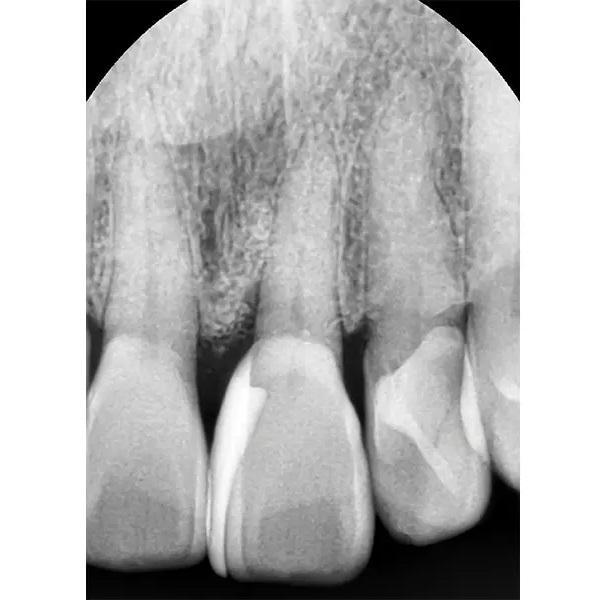

Фото 1. Предоперационный рентгеновский снимок. Стрелка указывает на пародонтальный дефект у зуба № 2.1.